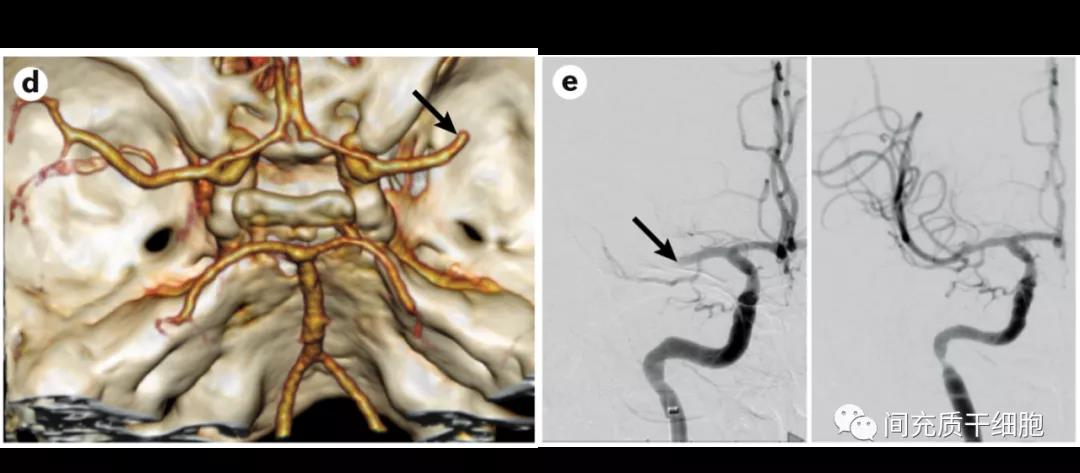

ͨ¹ýÄÔѪ¹ÜÔìÓ°¿ÉÒÔÈ·¶¨ÑªË¨µÄλÖ㬴Ӷø¼°Ê±´¦Àí¡£